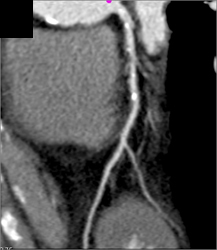

Diseased LAD